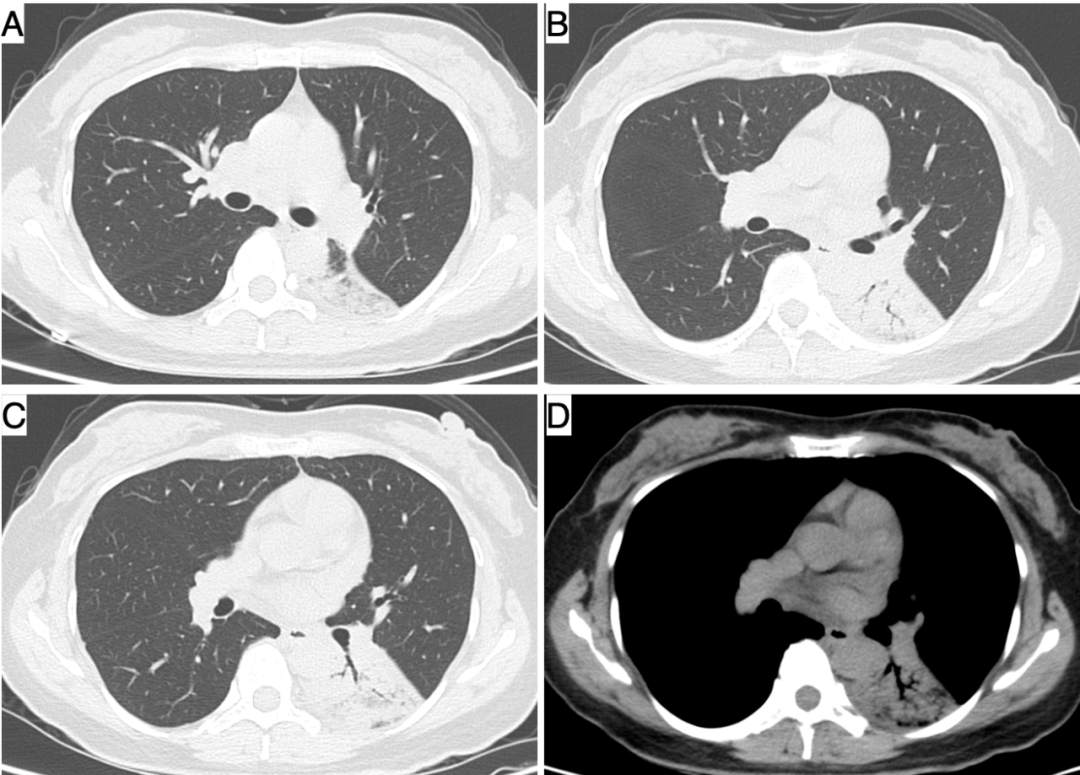

- 胸部 CT:左下肺实变(图 1)。

图 1 胸部 CT 示:左下肺实变伴支气管充气征,纵隔窗(D)实变中心未见低密度液性暗区(坏死)。